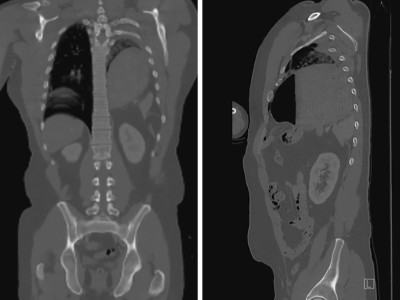

Doch kein Pneumothorax – schon mal so ein Trauma-CT gesehen?

Nach einem schweren Autounfall klagt der Fahrer über Atemnot und starke Schmerzen im linken Thorax. Linksthorakal fallen zudem ein fehlendes Atemgeräusch, ein dumpfer Klopfschall sowie eine Prellmarke auf. Es besteht der Verdacht auf einen Pneumothorax – bis der CT-Befund vier Organe auf Abwegen zeigt.

Ärzteteam führt Hüftoperation durch/© ATRPhoto / stock.adobe.com (Symbolbild mit Fotomodell), Orthopäde untersucht Patientin mittels Thomas-Handgriff /© Valle C et al. / all rights reserved Springer Medizin Verlag GmbH, Konservative Therapie bei Mittelhandbruch/© © Prof. Dr. Frank Unglaub, Gebrochener Arm eines Kindes erhält Gips/© Rafael Ben-Ari / stock.adobe.com (Symbolbild mit Fotomodellen), Indikationen zur konventionellen Bildgebung am Ellenbogen/© Rentschler V et al. / all rights reserved Springer Medizin Verlag GmbH, Gebrochener Fuß im Gips/© Aleksandr Kirillov / stock.adobe.com (Symbolbild mit Fotomodell), Knochensäge im Einsatz bei Knie-TEP/© Issara / stock.adobe.com (Symbolbild mit Fotomodellen), Läufer umfasst sein Sprunggelenk/© PeopleImages / Getty Images / iStock (Symbolbild mit Fotomodell), Rückenuntersuchung bei kleinem Mädchen/© Viacheslav Lakobchuk / stock.adobe.com (Symbolbild mit Fotomodellen), Aufziehen einer Spritze/© Eisenhans / Fotolia, Kinesiotape um das Knie herum/© baranq / stock.adobe.com (Symbolbild mit Fotomodell), Röntgenbild eines künstlichen Hüftgelenks/© Nicolas Larento / Fotolia, Arthropedia, Mobilisation nach Sprunggelenkfraktur/© T. Mittlmeier, Iliopsoas-Impingement/© Banke IJ et al. / all rights reserved Springer Medizin Verlag GmbH, MRT bei Epikondylopathia humeri radialis/© T. Leschinger, Traumatischer Enterothorax/© Besenbäck M et al. doi.org/10.1007/s10049-025-01537-0 unter CC-BY 4.0, Röntgen eines Ellenbogens mit Humerusfraktur/© Sampaio E et al. / all rights reserved Springer Medizin Verlag GmbH, Röntgen einer Beckenfraktur und Abdomen-CT bei Jugendlichem/© Karvouniaris N. et al. / all rights reserved Springer Medizin Verlag GmbH, Search Icon, Frau unkenntlich fasst sich ans Knie/© Pornpak Khunatorn / Getty Images / iStock (Symbolbild mit Fotomodell)